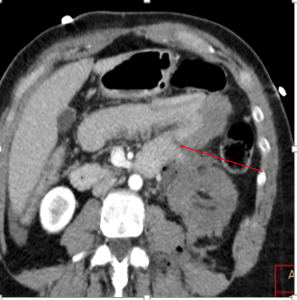

Conventional CT shows left kidney injury and transection of the doudeno-jejunal junction with focal intussusception.

Non-perfused left kidney with transected bowel at ligament of Trietz (red arrow)